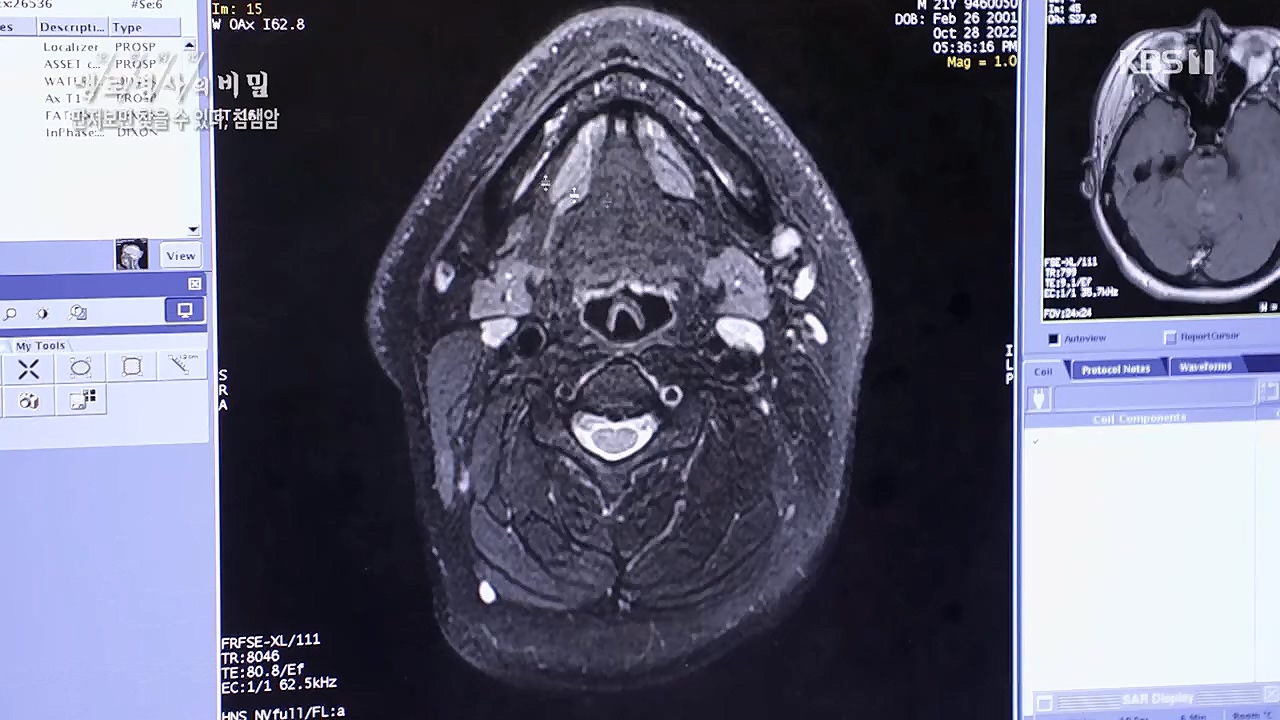

만져보면 찾을 수 있다 침샘암

양성종양이지만 크기가 쭉 성장하는 게 보여서

상당부분의 기능 손실을 어쩔 수 없이 가져가야 하는 상황이니다